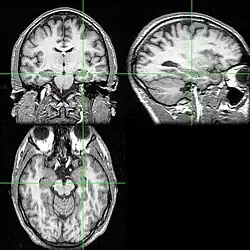

MRI indicating the hippocampus

Recent research using neuro-imaging technology including PET and fMRI scanning has shown that there is an extensive amount of distributed brain activation during the process of episodic encoding and retrieval. Among the various regions, the two most active areas during the constructive processes are the medial temporal lobe (including the hippocampus) and the prefrontal cortex.[15] The Medial Temporal lobe is especially vital for encoding novel events in episodic networks, with the Hippocampus acting as one of the central locations that acts to both combine and later separate the various features of an event.[16][17] Most popular research holds that the Hippocampus becomes less important in long term memory functioning after more extensive consolidation of the distinct features present at the time of episode encoding has occurred. In this way long term episodic functioning moves away from the CA3 region of the Hippocampal formation into the neocortex, effectively freeing up the CA3 area for more initial processing.[17] Studies have also consistently linked the activity of the Prefrontal Cortex, especially that which occurs in the right hemisphere, to the process of retrieval.[18] The Prefrontal cortex appears to be utilized for executive functioning primarily for directing the focus of attention during retrieval processing, as well as for setting the appropriate criterion required to find the desired target memory.[15]